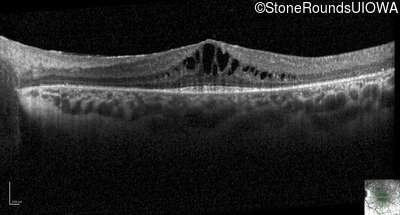

Optical Coherence Tomography - Right - 20/40

Exemplar / OCT Stack